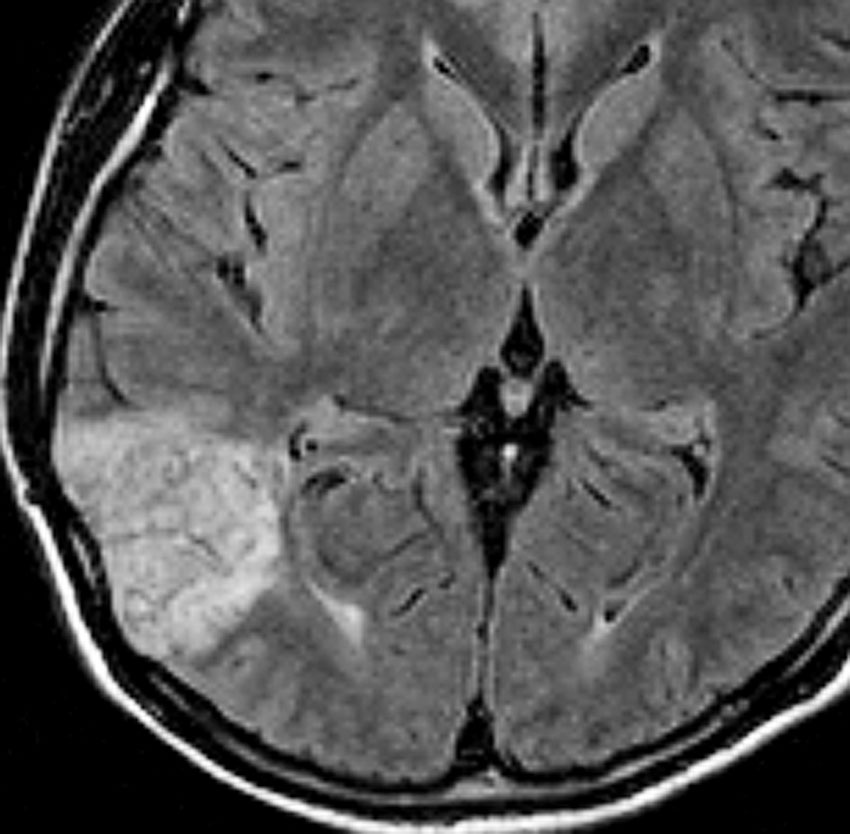

側脳室壁のあたりまで全摘出しました。とても柔らかい腫瘍で吸引できました。

病理は,粘液気質を背景に小型円形の核を有する細胞が増殖し,肺胞用構造を呈していました。その中にやや大型の神経細胞が多数混在するものです。